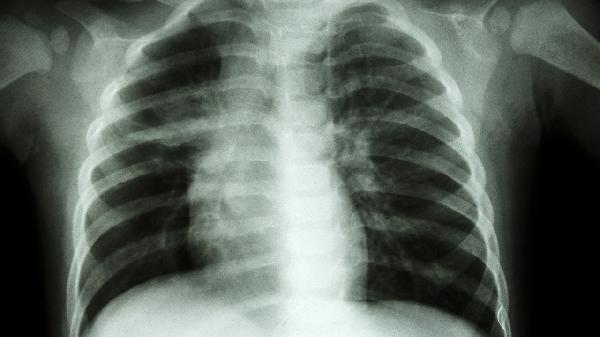

小儿鸡胸应挂儿科或儿童骨科进行专业诊断和治疗。鸡胸是一种胸骨前突的胸廓畸形,常见于儿童和青少年。其发生可能与遗传、营养不良、骨骼发育异常等因素有关。早期发现和干预对改善预后至关重要。

5、病理因素可能导致胸廓畸形。骨质疏松症、佝偻病等疾病可能影响胸骨发育。呼吸道疾病如哮喘长期未得到有效控制也可能导致胸廓变形。对于已有基础疾病的孩子,家长应积极治疗原发疾病,预防胸廓畸形。

治疗方法包括保守治疗和手术治疗。保守治疗包括佩戴矫正支具、进行物理治疗如扩胸运动和呼吸训练。食疗方面可多食用富含维生素D和钙质的食物如牛奶、鸡蛋、海产品。手术治疗适用于严重病例,常见术式包括胸骨翻转术、Nuss手术和Ravitch手术。手术可以有效矫正胸廓畸形,但存在一定风险,需在专业医生指导下进行。